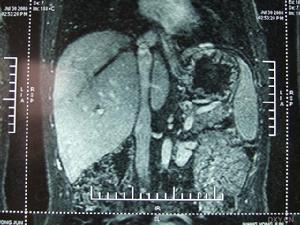

本CD-ROM為衛生部醫學CAI課件。本課件使用大量珍貴的臨床病例圖片、錄像、動畫和文字,配以解說,詳細介紹了布-加綜合徵(Budd-Chiarisyndrome)的臨床表現以及影像診斷,重點介紹其治療方法,主要包括適應證和禁忌證、介入治療器械、介入治療方法、最新進展、介入術後處理、併發症及處理。課件中附有練習題。課件內容豐富,資料寶貴,是學習布-加綜合徵的不可多得的輔助教材。本CAI課件由徐州醫學院製作,適用於醫學院師生以及臨床醫師學習使用。

病變累及肝靜脈或以上平面,則可有下腔靜脈高壓、門靜脈高壓(包括肝脾腫大、腹水、食管靜脈曲張和上消化道出血等)和心貯備功能不足(包括動則心悸、氣促)三組臨床表現。急性肝靜脈阻塞可因急劇進行性腹水、肝昏迷而死亡。

下腔靜脈阻塞綜合徵多數病人肝功能較好,白、球蛋白倒置或肝功能異常者約占1/3,可能由於此症肝細胞病理改變為繼發性,且程度較輕之故。